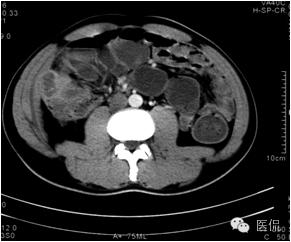

延迟期密度略有下降,但仍有强化,形态不规则。

手术病理诊断:

肝炎性假瘤,侵及周围结肠和腹壁,浸润组织有水肿,粘连。